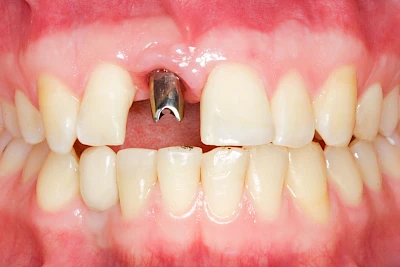

Implantate sind künstliche Zahnwurzeln. Nach einer gewissen Einheilzeit im Knochen (meist 3-6 Monate) erfolgt über einen separaten Aufbau (Abutment) die Befestigung einer Krone bzw. Brücke oder Zahnprothese.

In seltenen Fällen sind Implantate samt Aufbau aus einem Stück gefertigt. Auch gibt es Situationen, die ein Früh- oder sogar eine Sofortbelastung erlauben – dann kann die Einheilzeit der Implantate in den Knochen verkürzt oder sogar gänzlich darauf verzichtet werden.

Fehlen einzelne Zähne und die Nachbarzähne sind unbeschadet oder gut zahnärztlich versorgt, werden immer häufiger Implantate gewählt, um die Lücken zu schließen. Auch bei größeren oder verteilten Lücken, wenn keine herausnehmbare Prothese gewünscht ist, werden Implantate für Kronen- bzw. Brückenversorgungen gesetzt. In Einzelfällen entscheiden sich sogar zahnlose Patienten für eine festsitzende Versorgung auf Implantaten.